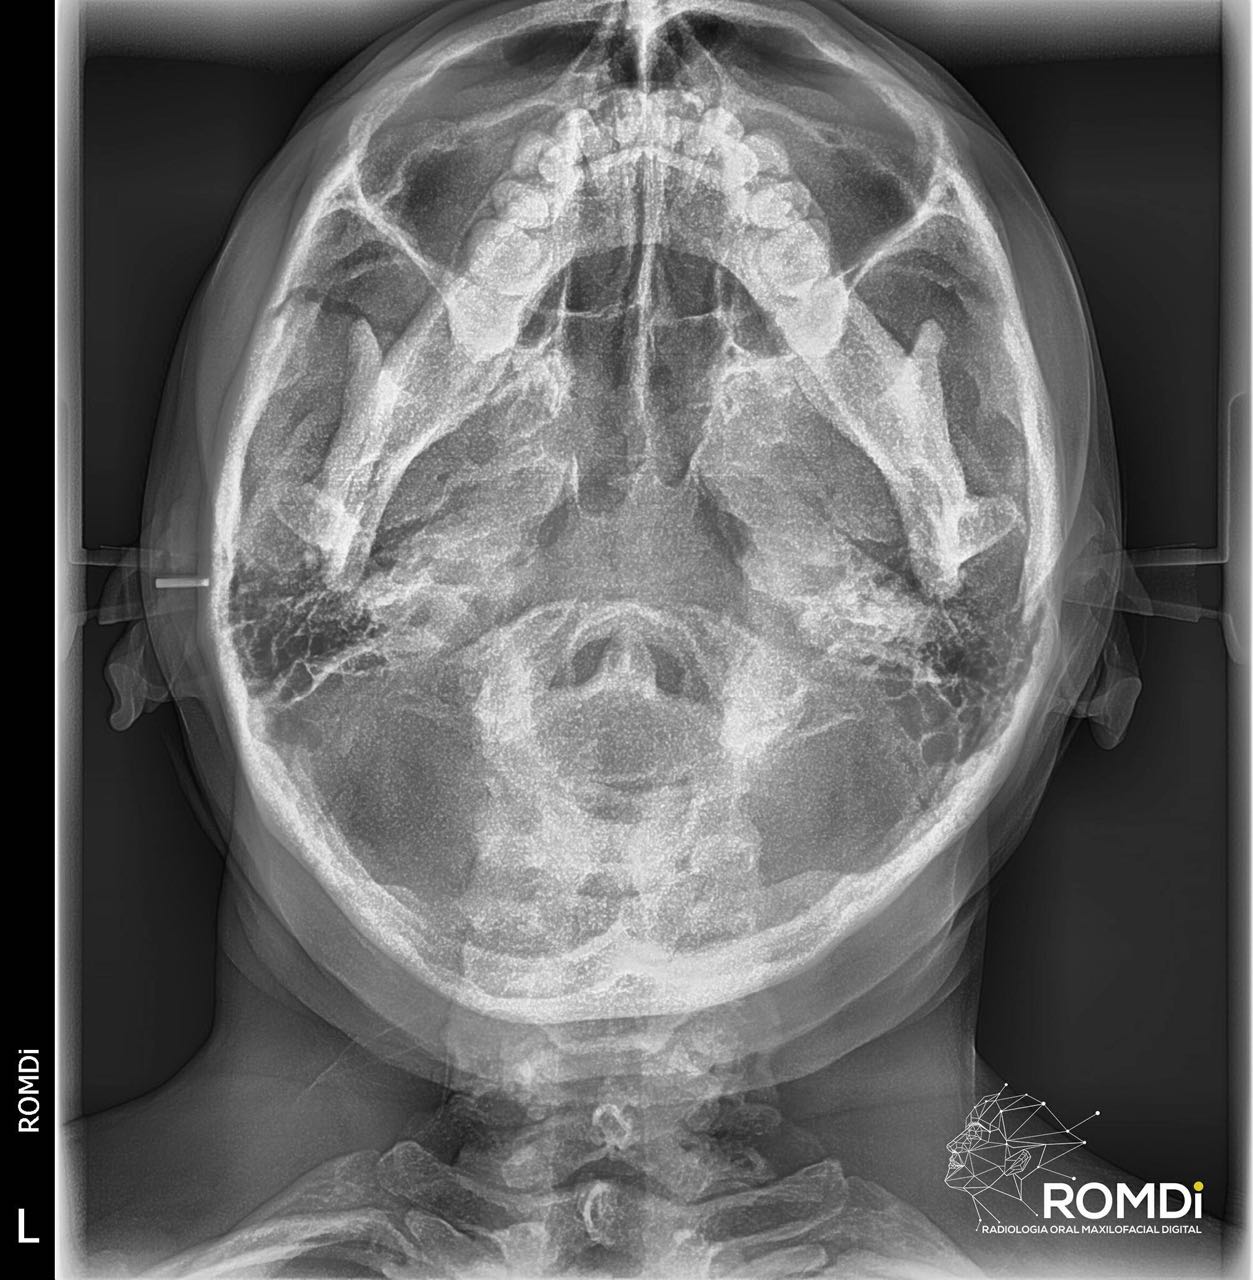

A través de la radiología, se conocen diferentes sistemas auxiliares de diagnóstico especializados de exploración, que nos proporcionan una información que ningún otro método nos puede ofrecer, tomando en consideración los avances técnico y científicos. En la materia de radiología, la actualización y aplicación de estos nuevos métodos, son necesarios para poder obtener el conocimiento básico y avanzado en el manejo de la interpretación radiográfica, así mismo, en conjunto con otros estudios clínicos, poder tener un diagnóstico acertado en las radiografías.

Nuestro equipo radiológico es de primera generación, con lo que podemos brindar a nuestro clientes imágenes médicas de alta calidad de manera rápida, ademas de contar con un servicio web que permite la distribución y almacenamiento digital en la nube.